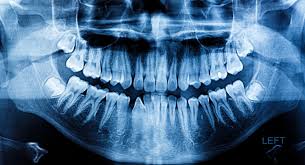

Osteosarcoma, the most common bone cancer, usually happens to people ages 10 to 30 and most often starts in the arms, legs, or pelvis. It depends on the location, but generally malignancies of bone will have an aggressive appearance with periosteal reaction, occasionally associated soft tissue mass component and surrounding edema of soft tissue and in the medullary canal. It often causes changes in patches of skin, such as thick growths. The tumor may extend into other bone tissue nearby like muscle or fat. Cancer of the floor of mouth often looks like an ulcer and is painless.

A Digital Manual For The Early Diagnosis Of Oral Neoplasia from screening.iarc.fr They may look like a patch or a lump or look like an ulcer. Some of the most common oral cancer symptoms and signs include: This aggressive type of cancer is more likely to spread to the lymph nodes A dry socket looks like a hole left after tooth extraction, where exposed bone within the socket or around the perimeter is visible. What bone metastasis looks like. Where the cancer is located, the bone might appear ragged or look like it has a hole. Cancer of the floor of mouth often looks like an ulcer and is painless. Abnormal cell growth usually appears as flat patches.